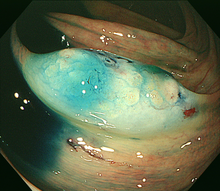

図 大腸がん

大腸がんとは

大腸がんは大腸の壁の最も内側にある粘膜内から発生します。大腸粘膜の細胞のいくつかの遺伝子に変異が生じることが原因と考えられ、発癌を促す遺伝子が現れたり,逆に発癌を抑えている遺伝子が働かなくなったりすることで癌が発生します。大腸がんの発生経路には,ほとんどの場合は良性の大腸ポリープである腺腫が大きくなる過程で癌に進展すると考えられていますが、正常粘膜から直接に癌が発生する経路もあると考えられています。大腸がんの約7割は直腸やS状結腸に発生します 。

大腸癌の肉眼型

大腸癌は見た目の形(肉眼形態)により,0型-4型に分類されています。0型(表在型)は早期がんで、1-4型は進行がんに分類されます。